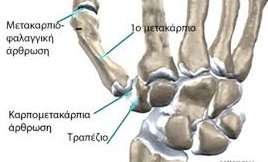

Ο καρπός του ανθρώπου περιλαμβάνει 8 οστάρια, τα οποία είναι τοποθετημένα σε δύο στίχους. Ο πρώτος στίχος περιλαμβάνει τα σκαφοειδές, μηνοειδές, πυραμοειδές και πισοειδές. Ο δεύτερος στίχος τα μείζων και έλασσον πολύγωνο, το κεφαλωτό και το αγκιστρωτό. Η απρόσκοπτη λειτουργία του καρπού εξαρτάται από την σταθερή και αρμονική σχέση των οσταρίων αυτών του καρπού μεταξύ τους, η οποία εξασφαλίζεται από την παρουσία ισχυρών συνδέσμων που συγκρατούν το οστά μεταξύ τους.